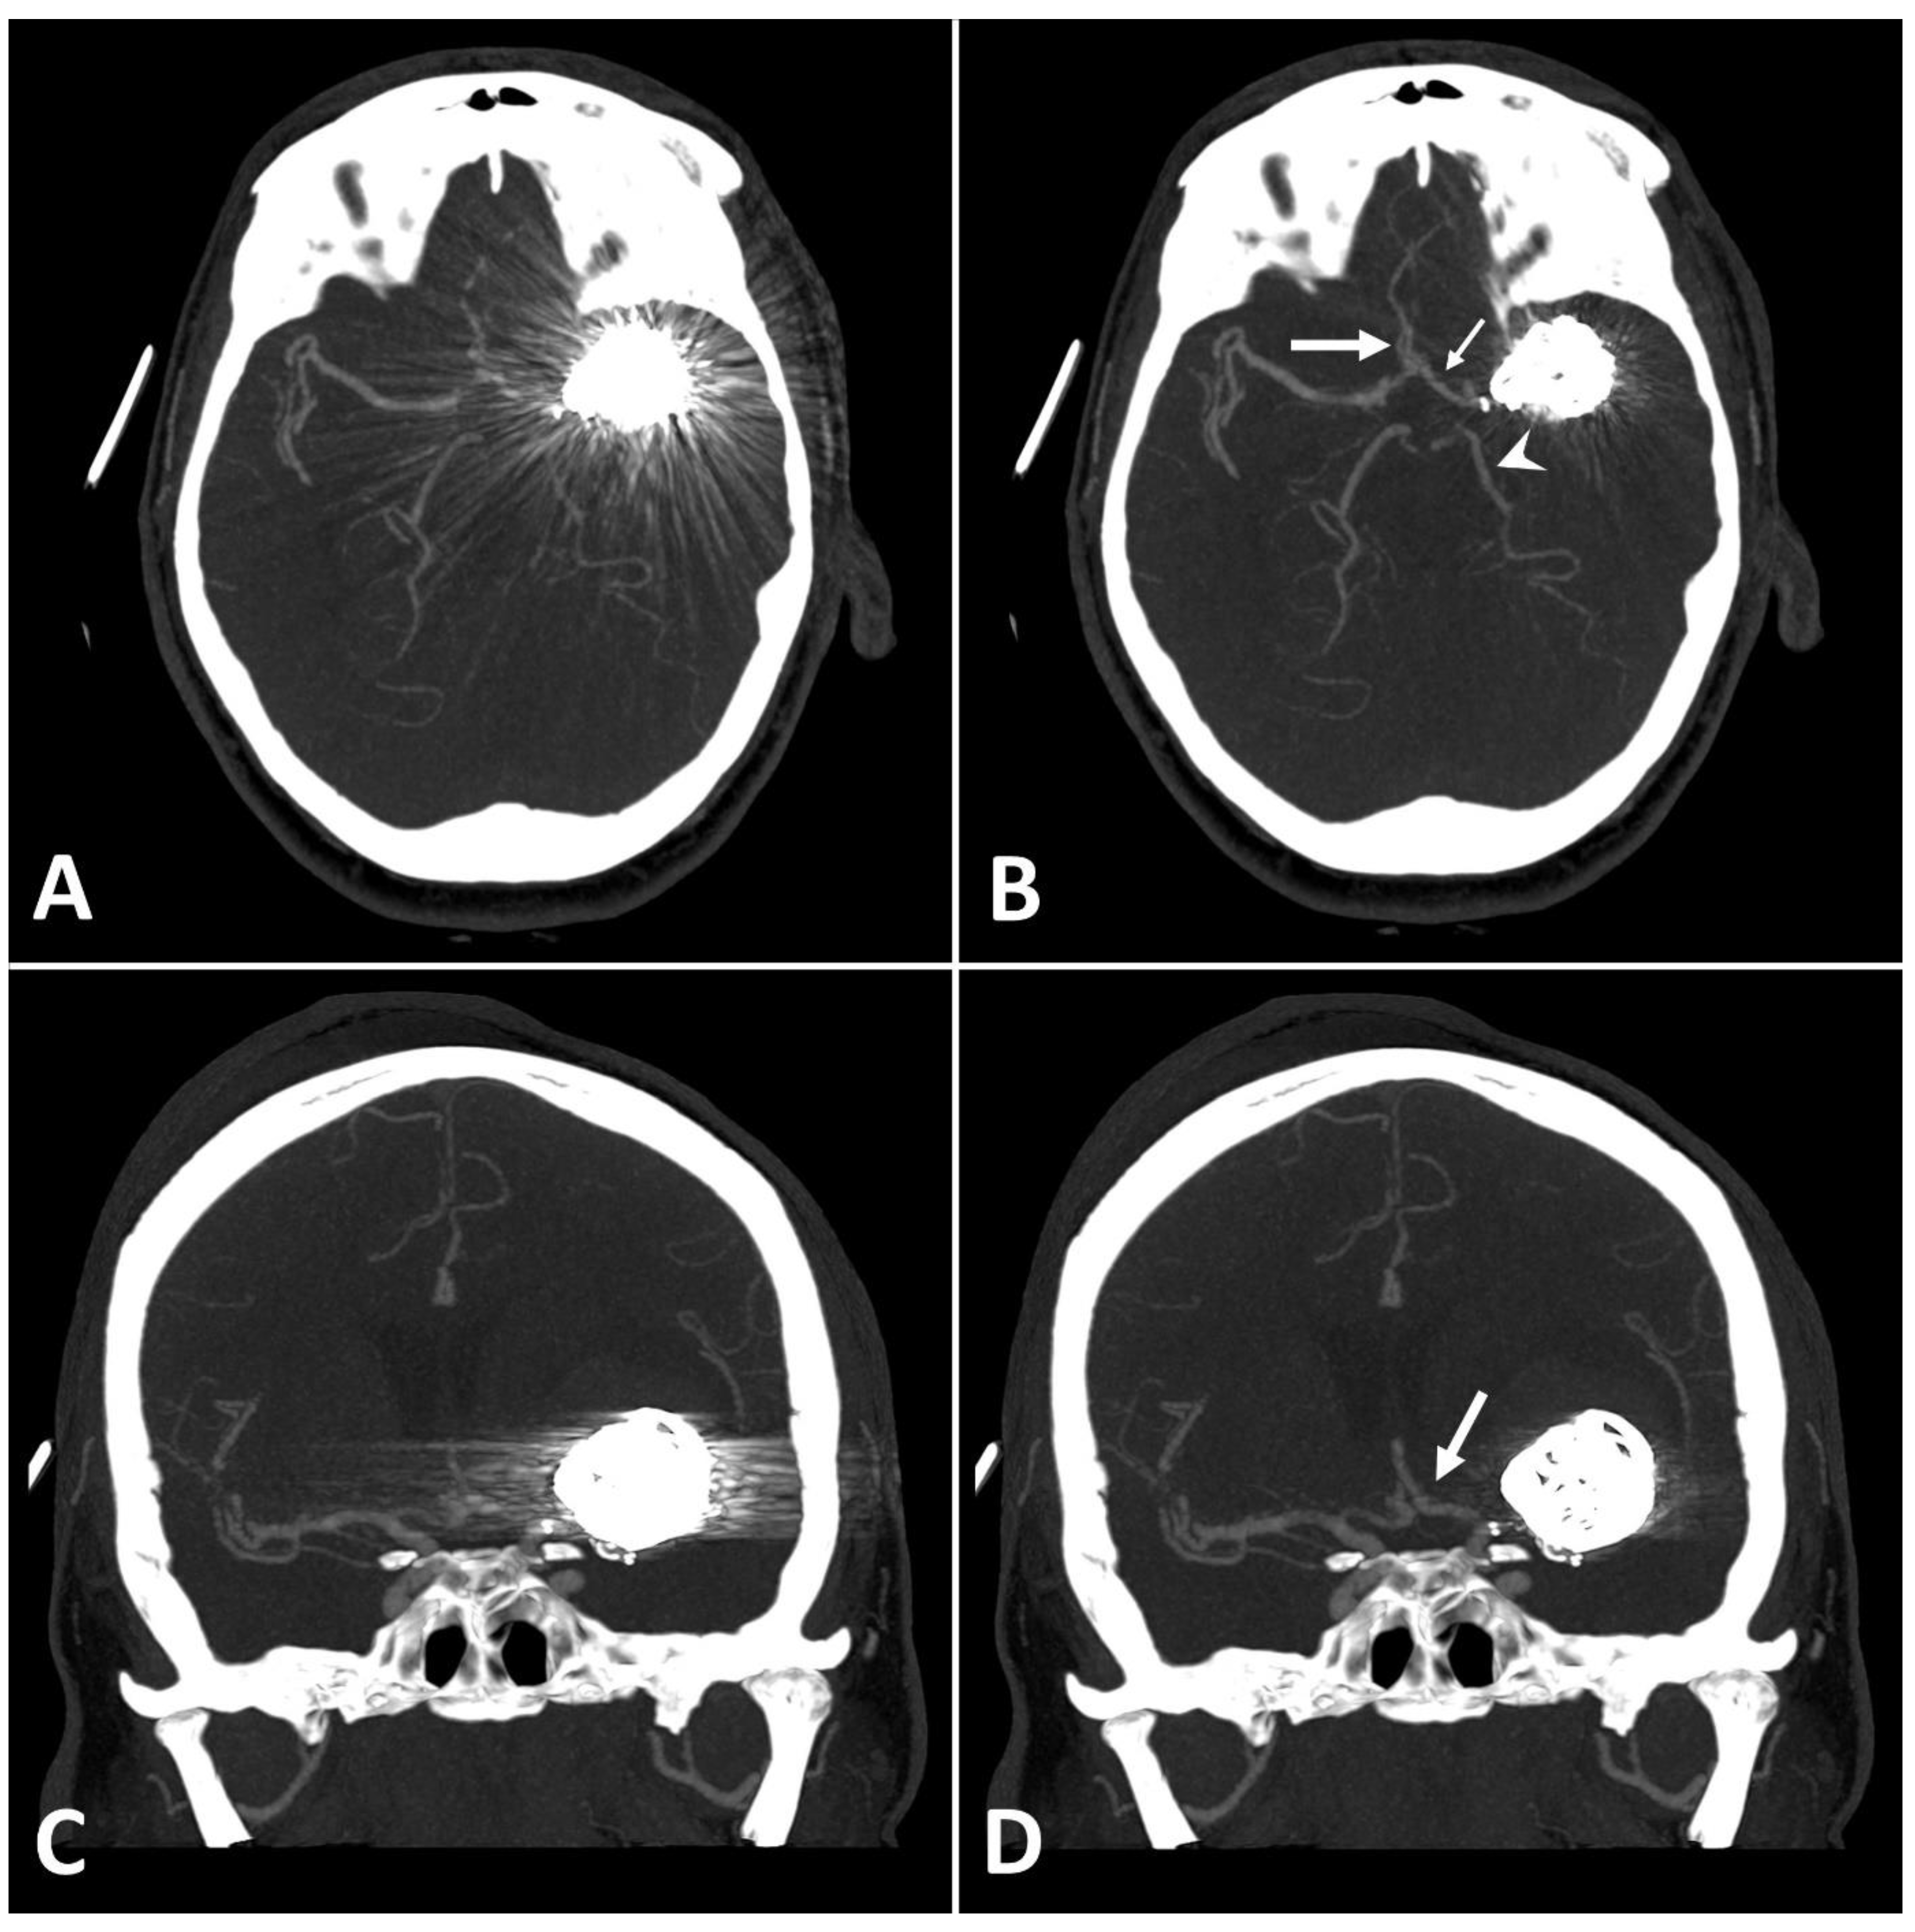

MAI in images with clips was significantly lower in close vicinity (SEMAR: 26.5 ± 55 vs. standard: 113.7 ± 95.4; p = 0.036) and more distally from the clip (SEMAR: 23.6 ± 6.5 vs. standard: 29.3 ± 16.8; p = 0.007). Figure 4 demonstrates the effects of SEMAR on images with clip-artifacts.

Figure 4.

(A,B): Exemplary follow up UHR-CT-angiography in axial plane without (A) and with SEMAR (B) of a 74-year-old female with an intracranial clip in the left middle cerebral artery. (C,D): Exemplary follow up UHR-CT-angiography in axial plane without (C) and with SEMAR (D) of a 63-year-old female with an intracranial clip in the right internal carotid artery. All images were reconstructed as MIP (Maximum Intensity Projection) with 12.5 mm slice thickness and demonstrate the effects of SEMAR on images with clip-artifacts.